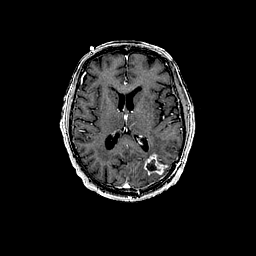

Glioma overlay -- Slice #64

[Home][Help][Clinical] Slice 64